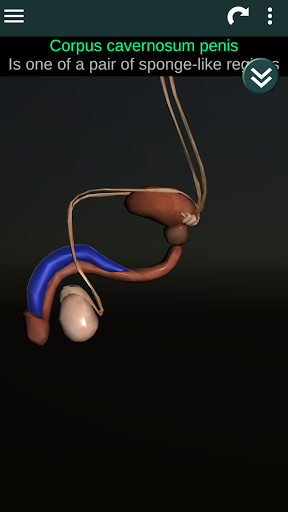

Menampilkan model anatomi 3D dari organ utama tubuh manusia dan penjelasannya masing-masing.

Apa yang ada di aplikasi?

* Sistem reproduksi, yang meliputi organ reproduksi pria dan wanita.